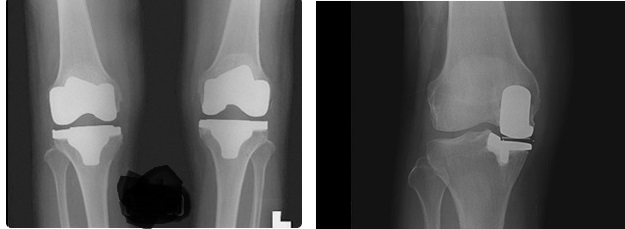

이와 달리 부분치환술은 최대한 환자의 인대와 구조물을 살리면서 관절염이 심한 곳의 조직만을 제거한 뒤 여기에 맞춰 인공관절 조직을 삽입하는 방법이다. 이 경우 환자는 전치환술에 비해 조직의 이물감을 덜 느끼며, 수술 다음날부터 목발 없이 걸을 수 있을 정도로 운동성도 좋은 편이다. 또 관절염이 발생한 부위만 선택적으로 수술하기 때문에 골 손실이 적어 향후 부작용이 생길 가능성이 적고, 문제가 생겨도 이후 다양한 치료가 가능하다.

하지만 모든 퇴행성관절염 환자가 부분치환술을 받을 수 있는 것이 아니다. 부분치환 수술이 이점이 많긴 하지만 다리가 바깥으로 휘어져 있다면 다리의 정렬 축을 맞추는 수술이 필요하고 정상인 나머지 관절이 나중에 손상되면 재수술을 해야 한다. 내외측 관절이 모두 손상되어있는 환자는 전치환수술을 받아야 한다.

김준한 정형외과 전문의은 “무릎 관절은 내측과 외측의 두 부위가 맞닿는데 대부분의 퇴행성관절염 환자는 내측 관절 조직부터 손상된다” 며 "원래 동양인의 다리가 O자로 조금 휘어 있어 내측 관절에 하중이 더 실리는 경향이 많은데 내측 관절만 망가진 환자는 이 부분만 고치면 되는데도 멀쩡한 조직까지 모두 잘라내는 전치환 수술을 하거나 약으로 버티는 경우가 많았다” 고 말했다.

따라서 수술 전 MRI 등을 활용한 정밀검사로 전방십자인대 등 무릎 전체 인대와 외측 관절이 건강한 지를 반드시 확인해야 한다. 검사 결과를 두고 전문의와 상담도 충분히 이뤄져야 한다. 환자의 상태가 부분치환술에 적합한지 정확히 판정할 수 있어야 하므로 임상 경험이 풍부한 전문의를 찾는 것이 중요하다. 부분치환 수술은 정상 연골과 이식한 인공관절이 완벽하게 균형을 맞춰야 하기 때문에 수술이 까다롭다. 김준한 원장은 "그래서 수술하는 의사의 경험에 따라 수술 결과가 천차만별"이라고 말한다.